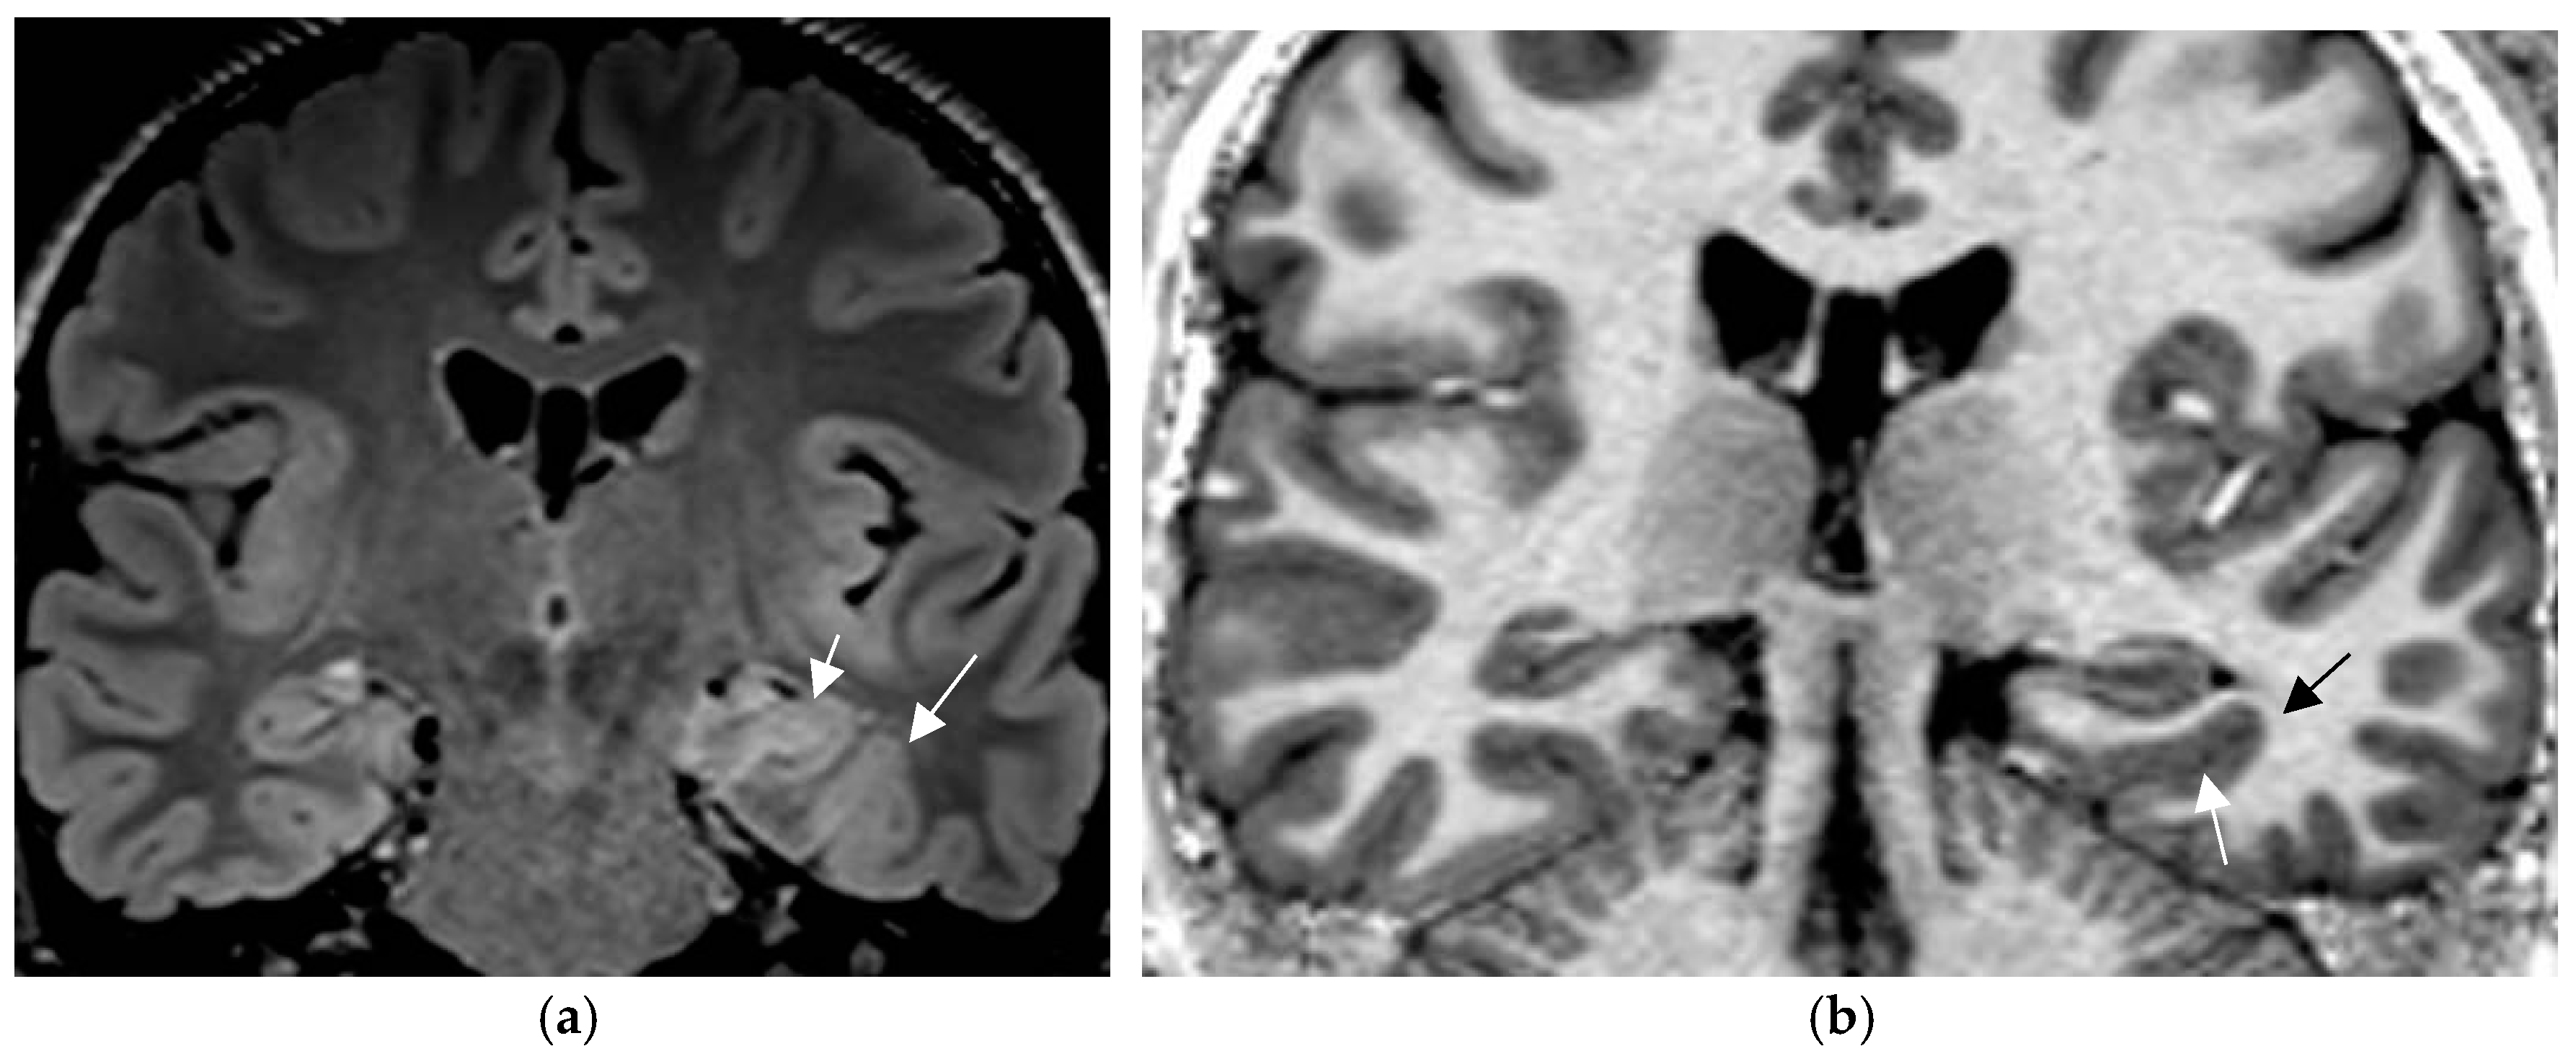

Postsurgical pathologic analysis of specimens of lesions missed by a negative brain MRI—even when performed using an epilepsy specific protocol—disclosed focal cortical dysplasia (FCD), hamartia, gliosis, and hippocampal sclerosis as the most common entities (Figure 1) [62].

Figure 1.

Histologically confirmed FCD I depicted by abnormal deep and straight left. collateral sulcus with a slight blurring of the gray–white matter junction on the FLAIR image. (a) (1.7 mm) and signal hyperintensity of the cortical border. Reduction of adjacent parahippocampal white matter (white arrow on MP2RAGE sequence) (b) slice thickness 0.9 mm. The hippocampus displays a mild signal increase on the FLAIR image (without atrophy) as a sign of dual pathology. Both lesions were missed on prior 1.5 T examination in a patient with left temporal lobe epilepsy.